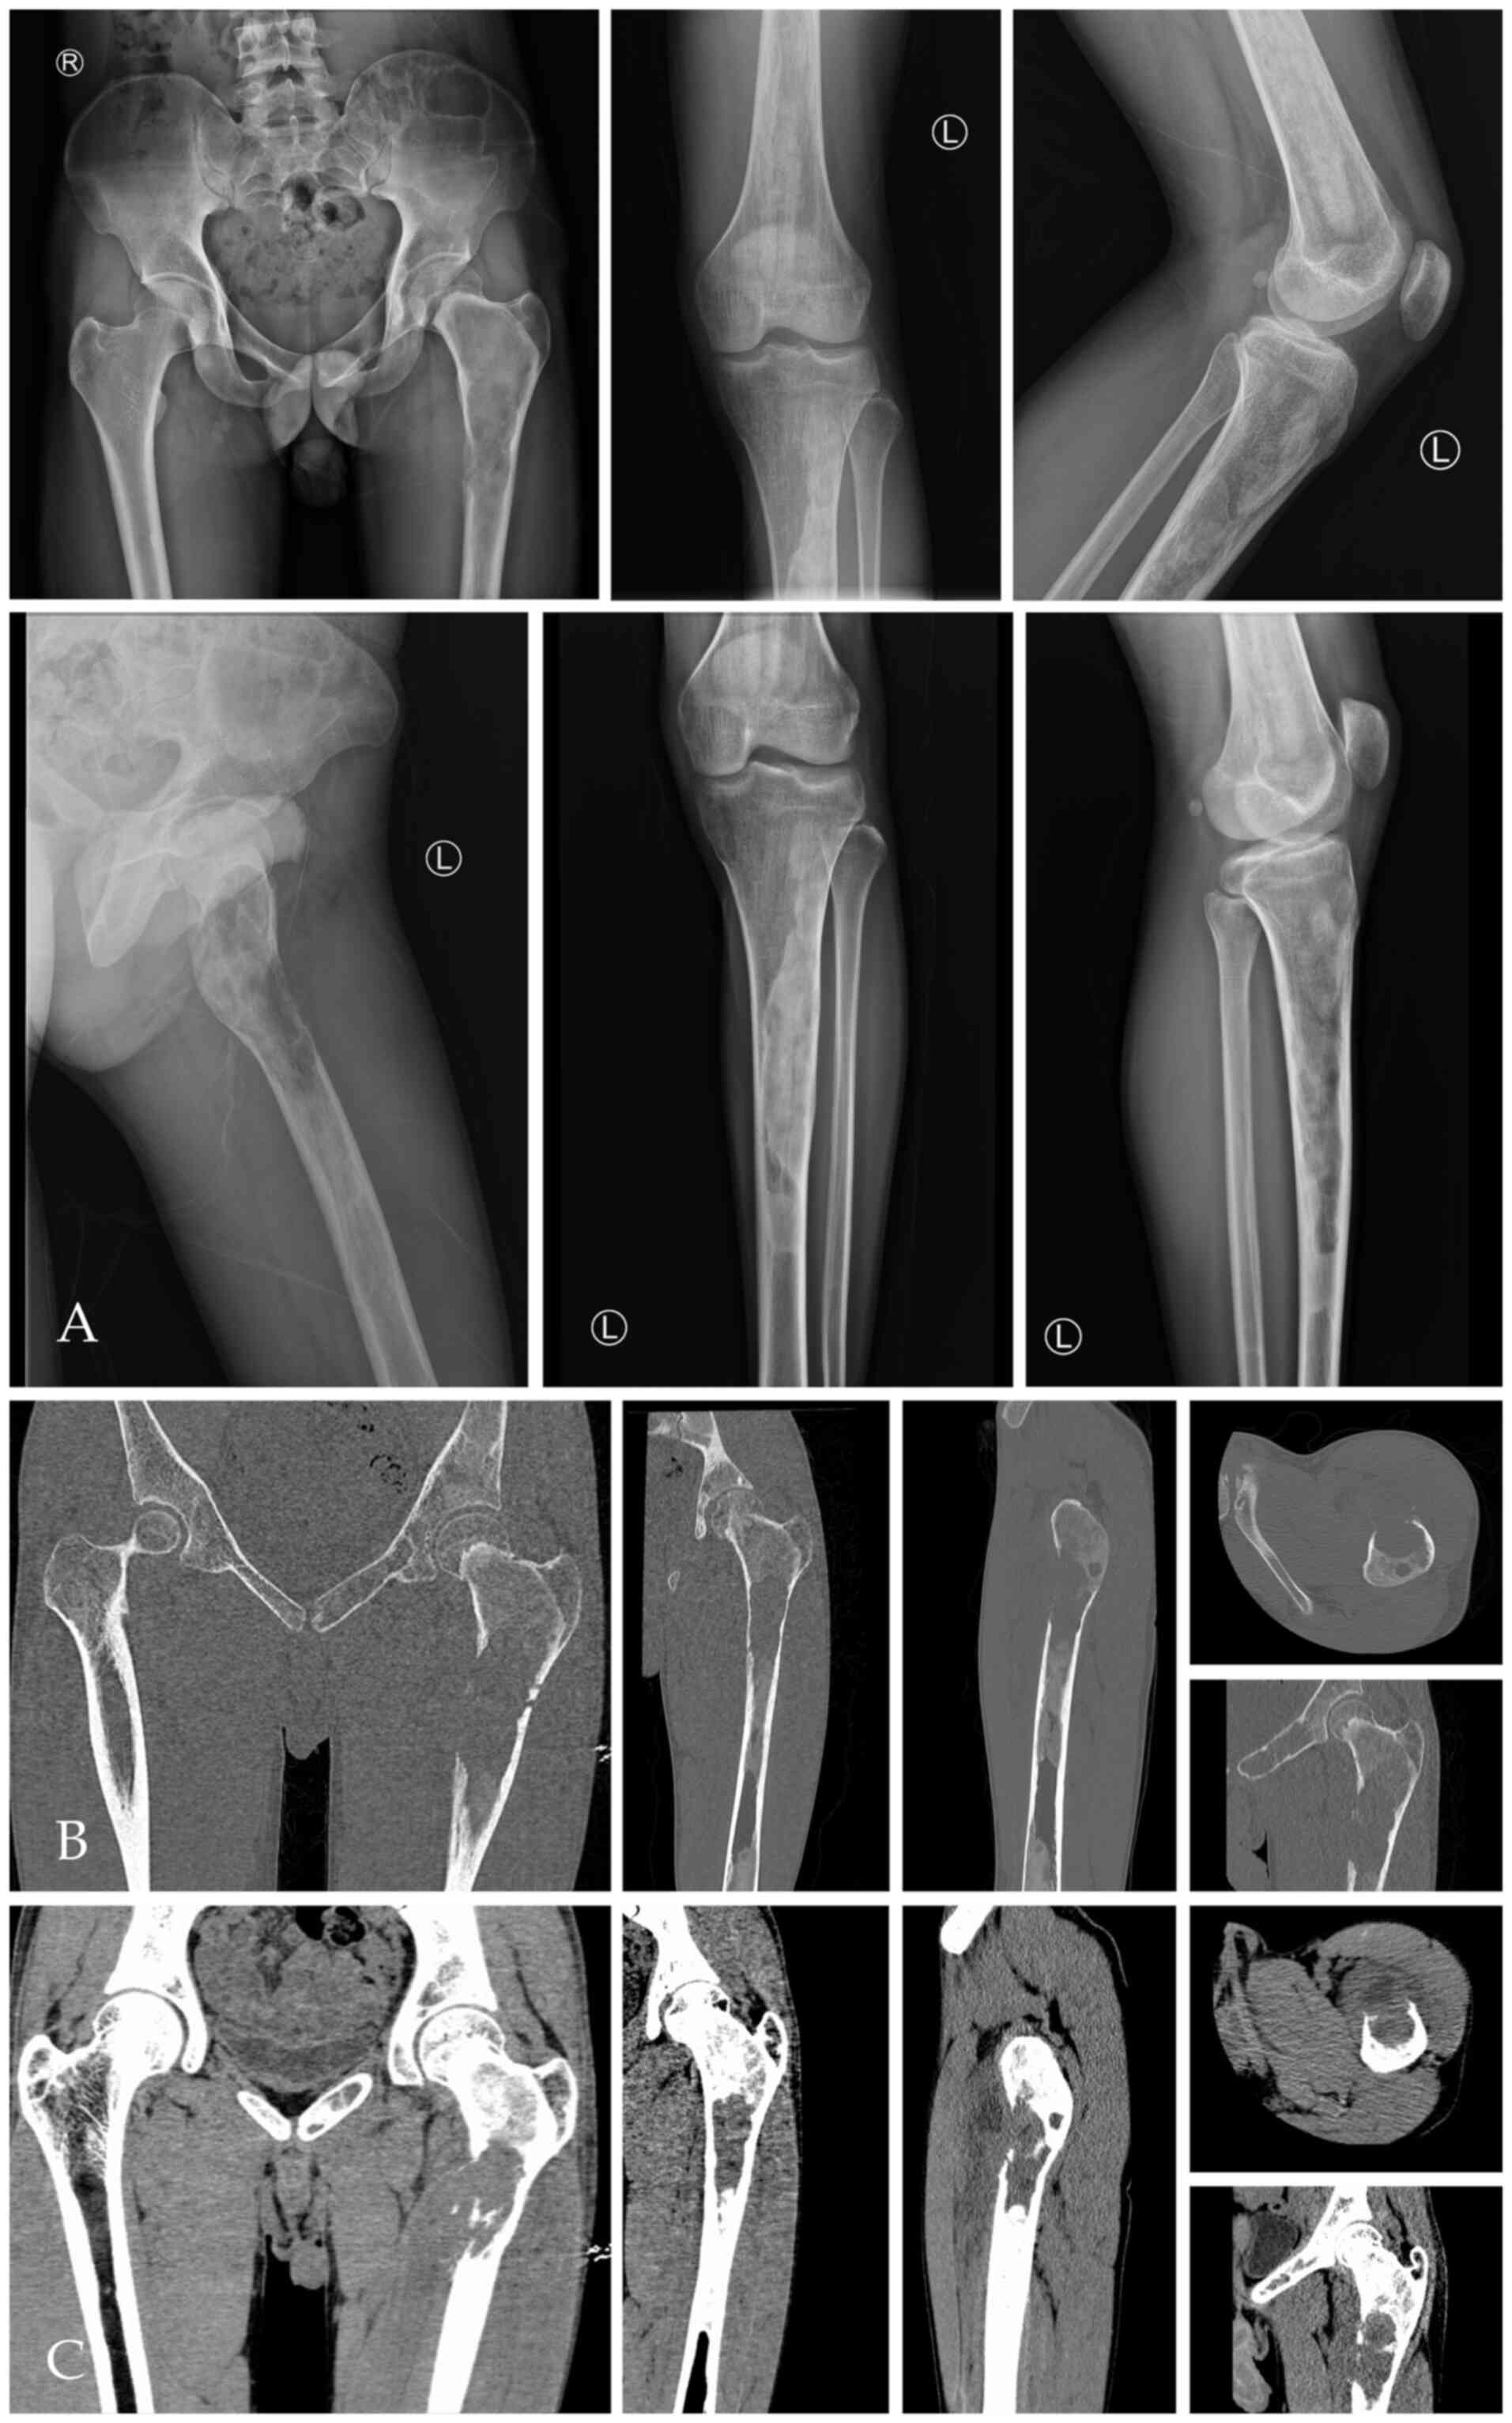

X-ray and CT of the left femur showed abnormal density of the left femur and the bone marrow cavity of the left hip, upper tibia and sacrum, and bone destruction of the anteromedial cortex of the left femur and formation of surrounding soft tissue masses (Fig. 1A-C). The possibility of malignancy was considered. MRI showed multiple bone destruction areas occupying most of the space of the marrow cavity with hypointensity on T1-weight imaging (T1WI), heterogeneous enhancement on contrast-enhanced T1WI, heterogeneous iso- and hyper-intensity on T2WI, and heterogeneous signal intensity on T2-weight spectral attenuated inversion recovery (T2W-SPAIR).

Figure 1

X-ray and CT of fibrous dysplasia of bone with malignant transformation. (A) X-ray and (B) bone window CT images showed low-density areas of multiple bone destruction and ground-glass high density in the left hip and upper femur bone marrow cavity. (C) Venous phase (a phase of contrast-enhanced CT) of soft tissue window of the left femur shows destruction of cortical bone with formation of soft tissue masses around the left upper medial femur with heterogeneous enhancement.

These features indicated local bone destruction, swelling of surrounding soft tissue and soft tissue invasion (Fig. 2A and B). In the upper left femur, an irregular mass was seen in front of the upper left femur, which broke through the cortex and protruded into the surrounding soft tissue (Fig. 2C). 99mTc-MDP three-phase bone imaging was recommended to confirm the blood supply and abnormal uptake of 99mTc-MDP. The areas of bone and marrow surrounding the greater trochanter and the neck of the left femur showed increased blood perfusion on the perfusion and blood pool phase, while bone marrow destruction areas in MRI showed higher amounts of blood perfusion in the upper femur (below the greater trochanter) (Fig. 3A and B). However, the levels of tracer uptake of the two areas were reversed in the delayed phase and were clearer on tomography. The other tracer uptake lesions in the left pelvic and lower limb bone corresponded to an ill-defined radiolucent lesion on X-ray (Fig. 3C and D).